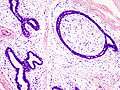

| Histopathologic image of breast fibroadenoma. Core needle biopsy. Hematoxylin & eosin stain. | |

Histopathologic image of breast fibroadenoma. Core needle biopsy. Hematoxylin & eosin stain.